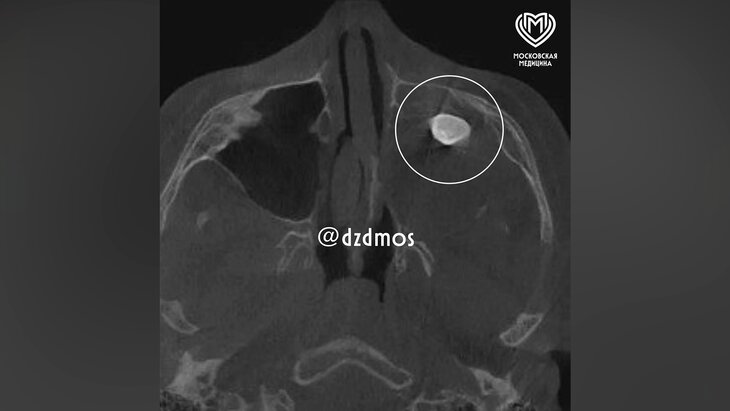

Подросток поступил в больницу с жалобами на асимметрию лица и заложенность носа. Выяснилось, что у пациента в гайморовой пазухе сформировался зуб. Это обнаружили еще в частной больнице, и родители ребенка решили обратиться за консультацией в Филатовскую больницу.

Во время операции специалисты обнаружили новообразование, внутри которого находился зуб. Образование удалили полностью и направили на исследование. Выяснилось, что это тератома – эмбрионально-клеточное новообразование, внутри которого могут находиться элементы тканей, несвойственные этому участку тела: волосы, ногти, мышечные волокна, кости или зубы.

Такие новообразования редко встречаются в зоне лица, чаще в крестцовой области. Ни КТ, ни рентген новообразование не показали, поскольку оно занимало фактически всю левую полость носа.